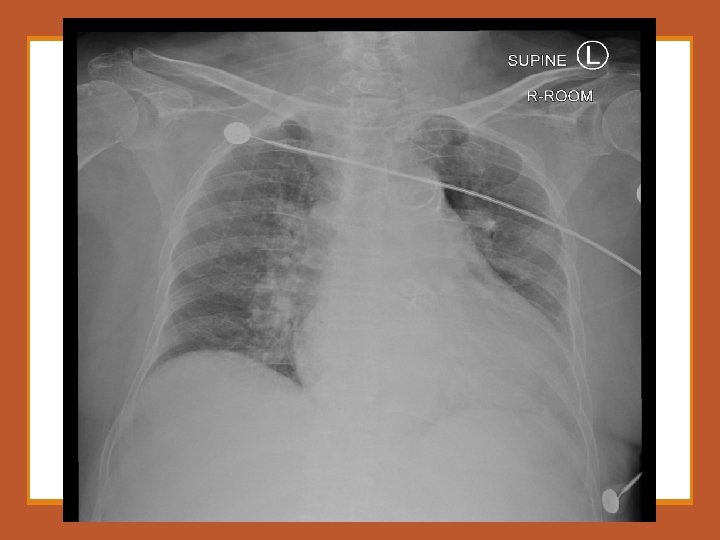

1. Please comment on the ECG and CXR.

2. What is your working diagnosis?

An urgent CT aortogram was ordered. Please comment on the images.